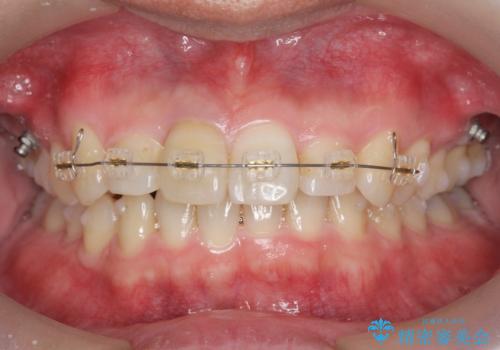

2級ディープバイト 遠心移動を伴うマウスピース矯正

- 前歯のがたつきを改善したい、と矯正治療を希望され来院されました。

・深い噛み合わせ(ディープバイト) ・2級性の咬合関係(上顎前突)・前歯のがたつき

以上のような歯並びの問題をマウスピース矯正インビザライン・カリエール・マイクロインプラント・部分ワイヤー矯正

を用いて改善していきます。

深い噛み合わせと上顎前突の状態を治すのに時間がかかりましたが、治療後は理想的で安定した咬合関係となりました。